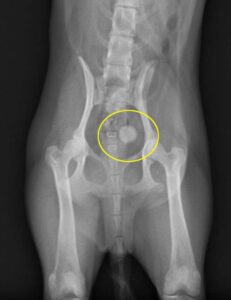

血尿・頻尿の症状で来院されました。レントゲン・エコー検査にて、膀胱内に結石を認め、手術による摘出となりました。無事手術も終わり元気に退院しました。その後は処方食にて再発もなく順調です。よかったね。